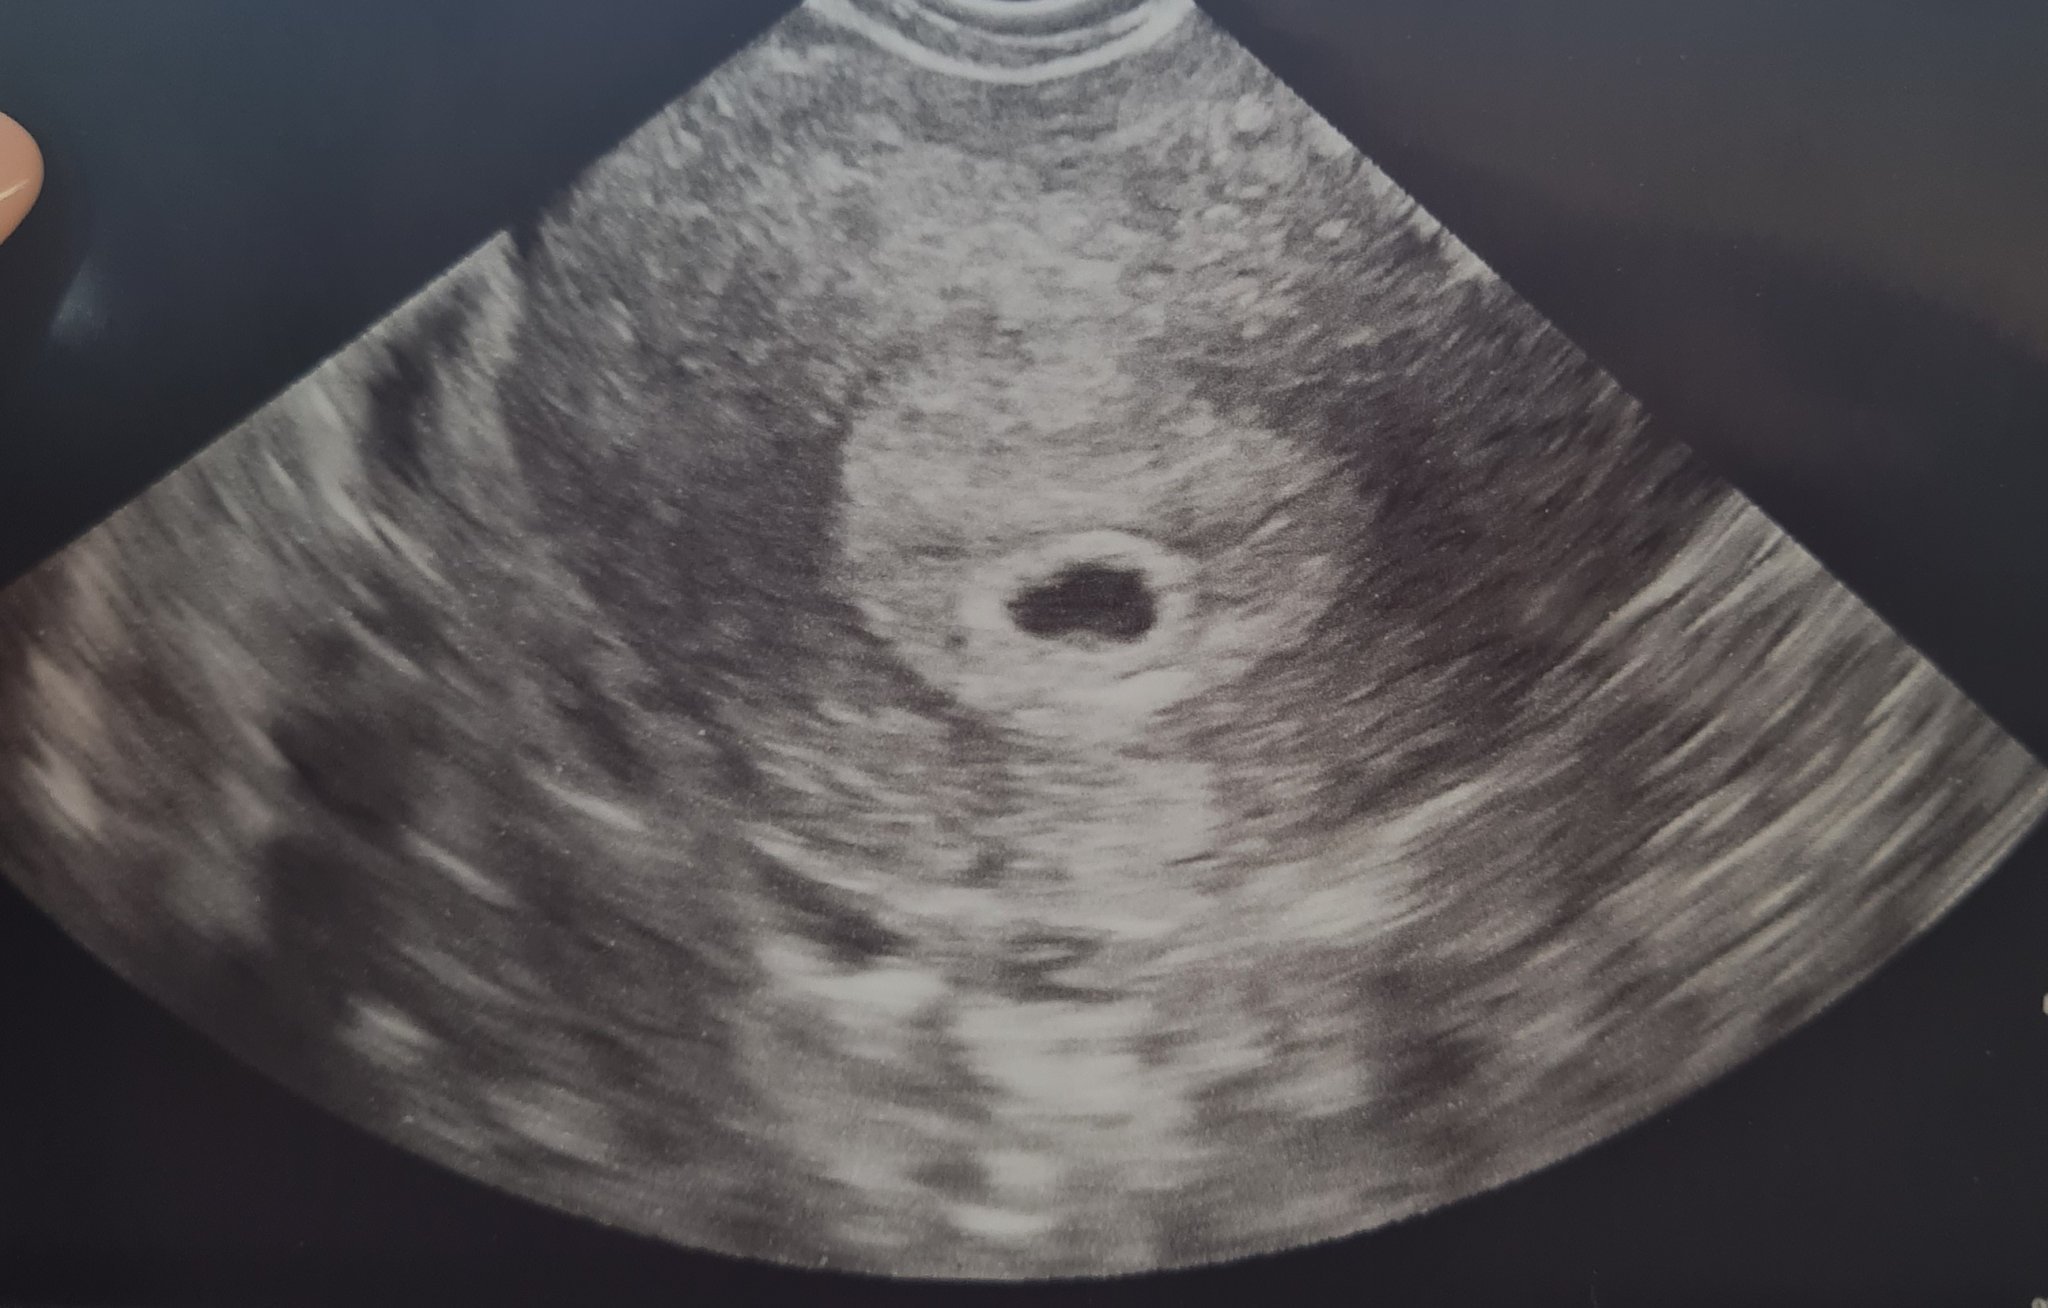

Момичета днес сутринта пак пуснах чхг ...3620...Следобед бях на преглед и се видя най- накрая плоден сак в матката. Камък ми падна от сърцето....Но зацапването продължава и сега ми назначиха терапия с пролутекс и зарзио. Благодаря ви за подкрепата.

ПП: Докато пишех и AsisA публикува снимката Simple Smile